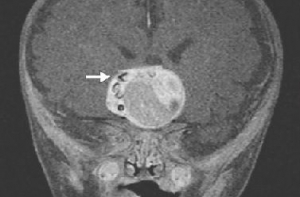

Сканирование мозга выявило наличие опухоли, содержащей структуры, напоминающие зуб из нижней челюсти. Пришлось провести операцию для удаления опухоли. Именно во время оперативного вмешательства врачи подтвердили: в мозге действительно был зуб. Опухоль располагалась рядом с гипофизом.

Медики диагностировали краниофарингиому - редкий тип рака мозга. Такие опухоли могут вырастать до больших размеров, но не распространяются. Что касается зуба, специалисты никогда не находили подобных структур в краниофарингиомах. В данный момент ребенок проходит реабилитацию и чувствует себя хорошо.